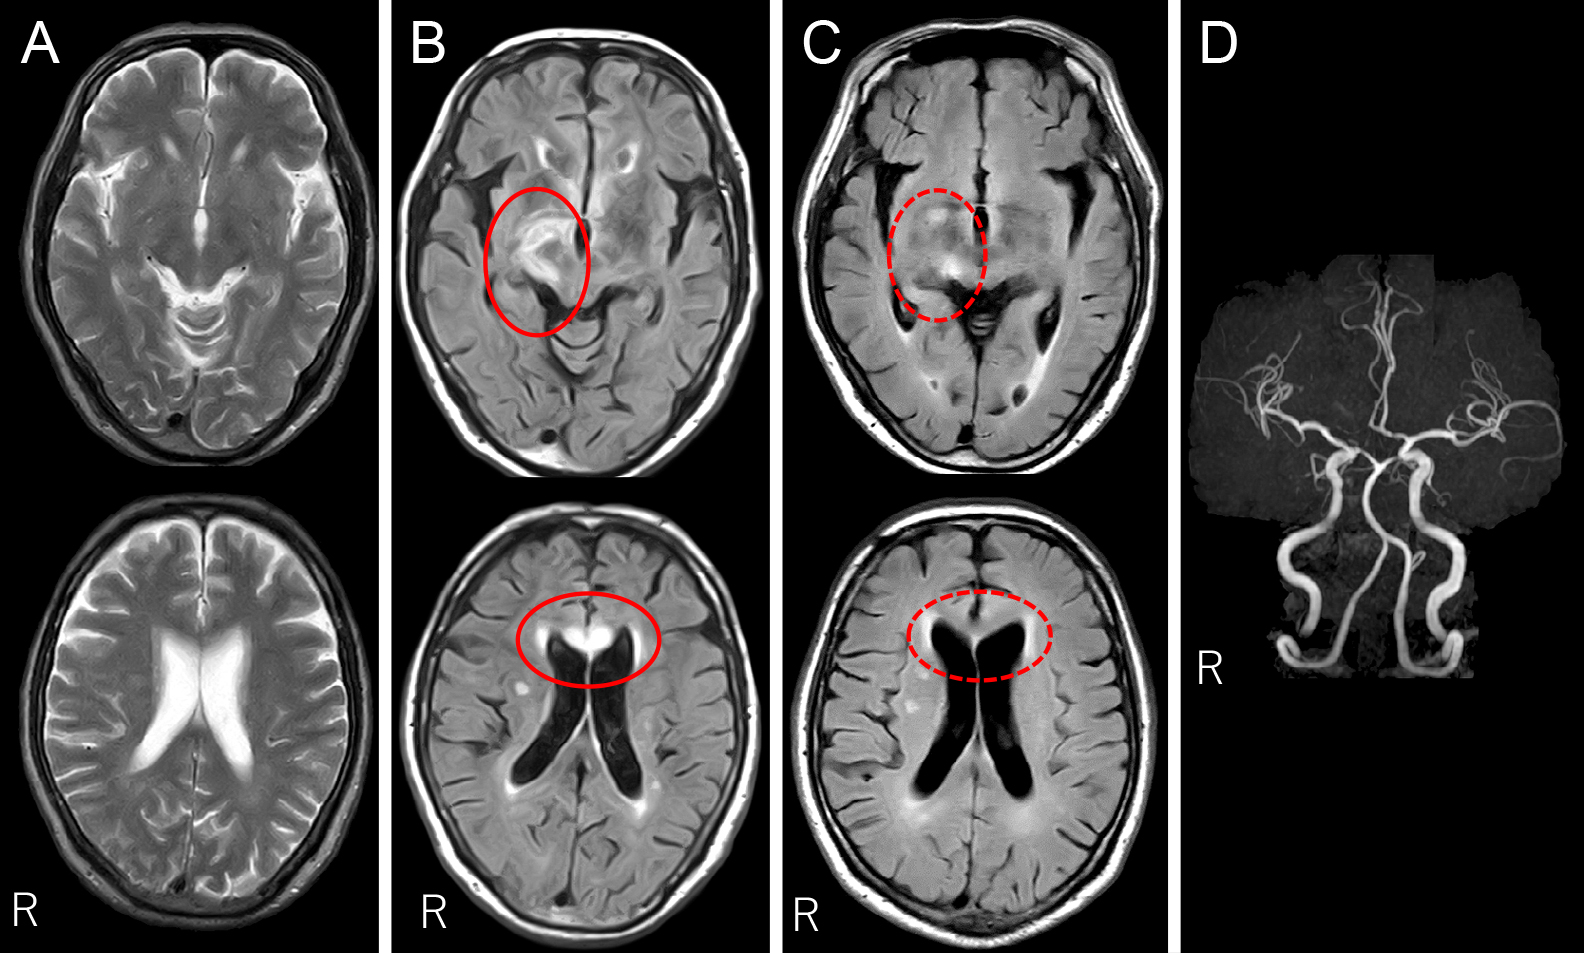

Claustrum signを呈したfebrile infection related epilepsy syndrome(FIRES)の55歳女性例

Febrile infection-related epilepsy syndrome (FIRES) with the claustrum sign in a 55-year-old woman: a case report

赤尾 剛, 市川 大, 藤盛 寿一, 中島 一郎

Go Akao, Dai Ichikawa, Juichi Fujimori, Ichiro Nakashima

2026/03/11